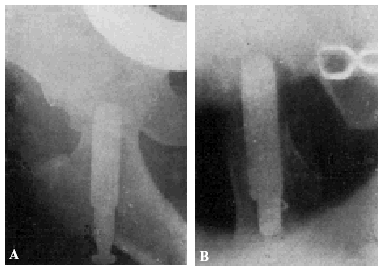

Con buena técnica, todos los resultados son favorables, a pesar de que al cabo de algunos años exista un grado más o menos acentuado de artrosis (véanse la observación núm. 4, fig. 7., A y B, y la observación núm. 9, fig., 8. A, B y C), que corresponden a los dos enfermos que hace más tiempo que están operados, y que en la actualidad aún viven.

Figura 7. A: obs. núm. 4. Enfermo de sesenta y cuatro años, operado en noviembre de 1935. La situación del clavo puede aceptarse como buena (ligeramente craneal). B: obs. núm. 4. Radiografía del mismo enfermo de las dos figuras anteriores, practicada en la actualidad (julio de 1943). Artrosis manifiesta. La cabeza del fémur tiende a aplastarse. Deambulación perfecta.

Figura 8. A: obs. núm. 9. Enferma de cuarenta y cinco años, operada en enero de 1937. El clavo procedía del cadáver de la observación mencionada como fracaso número I, y presentaba unos ligeros depósitos de herrumbre. La situación del clavo es buena. B: obs. núm. 9. El mismo caso de la figura anterior. En proyección lateral también es perfecta la situación del clavo. Éste tuvo que ser extraído a los siete meses de intervenida la fractura, a causa de una persistente supuración. C: obs. núm. 9. Radiografía del caso de las dos figuras anteriores, practicada en julio de 1943. Artrosis muy ligera. El cuello del fémur parece muy estrechado, pero esta deformidad también puede apreciarse en la figura B. Deambulación perfecta.

No consideramos como un fracaso el tener que sacar el clavo, maniobra que hemos practicado en tres casos (en la obs. núm. 9, fig. 8., A, B y C; la núm. 30, C y D, y núm. 18, fig. 17, A y B) que hemos citado anteriormente, en el cual la extracción provocó el exitus letalis.

Muchos fracasos de Böhler se deben a haber cargado precozmente la extremidad. La figura 15, A y B8, corresponde a un fracturado operado por Böhler. El clavo está bien colocado en las dos proyecciones, aunque es poco profundo y ligeramente ventral en lugar de dorsal. A los dos meses, cuando el enfermo andaba perfectamente bien, nota el enfermo bruscamente dolores y se comprueba a la exploración radiográfica que el clavo se había salido de la cabeza del fémur (fig. 15, C y D). Dice Böhler, referente a este caso: «Este desprendimiento no habría ocurrido si el clavo se hubiera colocado algo más caudal y más dorsal respecto a la línea media del cuello y de la cabeza y, a la vez, hubiese penetrado lo suficiente en ésta». Y añadimos nosotros: a pesar de que la situación del clavo no era idealmente perfecta en este caso, la culpa del fracaso reside fundamentalmente en la carga precoz del miembro fracturado. Si observamos la figura 16, A y B (observación núm. 23), aunque en proyección anteroposterior, la situación del clavo puede considerarse perfecta; en proyección lateral, está en situación mucho más ventral que la observación anterior de Böhler, y sin embargo la enferma, operada en mayo de 1941, anda en la actualidad, a pesar de sus setenta y ocho años, sin la ayuda de ningún bastón y sin presentar ninguna molestia (fig. 16 C). La situación del clavo en este caso es muy semejante a la de la enferma citada anteriormente, que falleció al extraerle el clavo intolerante (supuración de la herida, sin síntomas generales de infección) (fig. 17 A y B; obs. núm. 18), por lo que todo hace suponer que, en caso de no haberse presentado el desenlace fatal, el resultado funcional hubiera sido bueno.

Figura 15. A: comprobación roentgenológica después de colocar el clavo e impactar los fragmentos. La diástasis entre éstos ha desaparecido. El clavo está en el centro del cuello y de la cabeza, pero no lo suficiente profundo, puesto que su punto dista 13 mm. de la superficie de la cabeza, en vez de 3 a 6 mm. B: en la proyección lateral, el clavo está colocado algo hacia delante, es decir, demasiado ventral, en la cabeza del fémur. (De Böhler Jeschke.)

Figura 15. C y D: al principio andaba perfectamente, pero de pronto se le presentaron dolores, y en la roentgenografía se vio que el clavo se había salido de la cabeza del fémur y los fragmentos habían vuelto a desviarse a la posición que tenían antes de la reducción. Este desprendimiento no habría ocurrido si el clavo se hubiera colocado algo más caudal y más dorsal respecto a la línea media del cuello y de la cabeza, y, a la vez, hubiese penetrado lo suficiente en ésta. (De BöhlerJeschke.)

Figura 16. A: obs. núm. 23. La situación del clavo en esta proyección es buena. B: obs. núm. 23. El mismo caso de la figura anterior, en proyección lateral. La situación del clavo es excesivamente ventral. C: Obs. núm. 23. El mismo caso de la figura anterior, en la actualidad. A pesar de la artro-sis existente, la enferma no presenta la más mínima molestia ni se halla limitada la movilidad articular.

Figura 17. obs. núm. 18. La fractura está enclavada en valgus. El clavo está bien colocado, aunque es algo corto. B: obs. núm. 18. El mismo caso de la figura anterior, en posición lateral. El clavo, algo corto, está colocado en la misma posición defectuosa que el caso de la figura 16, B.

Figura 18. A: obs. núm. 33. La situación del clavo de Böhler es ligeramente craneal y ha penetrado demasiado profundamente. B: obs. núm. 33. El mismo caso de la figura anterior, en proyección lateral. El alambre de Kirschner, vertical, se ha desclavado de la cabeza. Esto ha sido la causa de la situación excesivamente ventral del clavo. (Véase la figura siguiente.) C: obs. núm. 33. (Véase la figura anterior.)